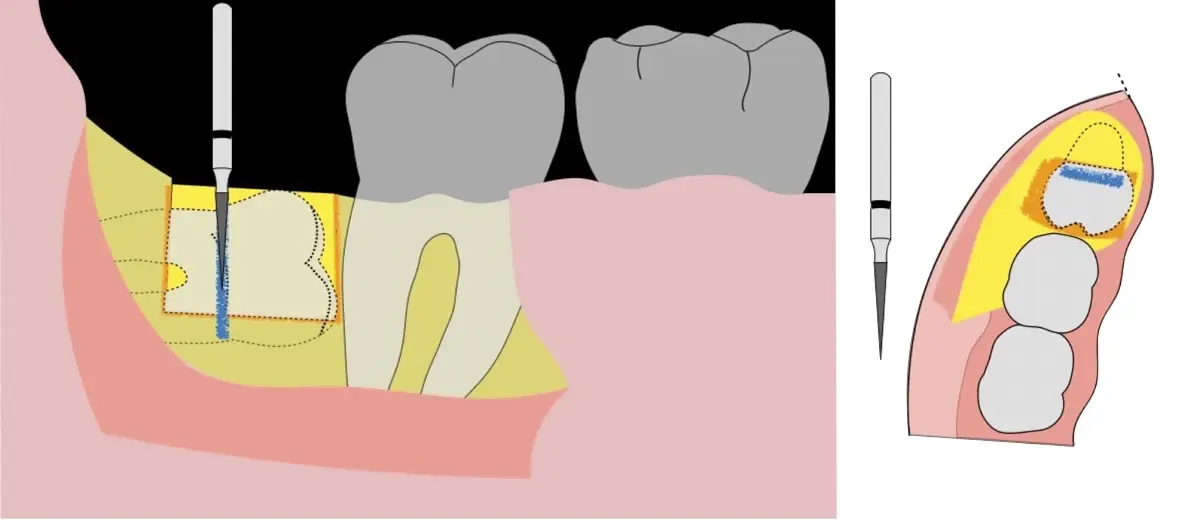

El procedimiento se inicia colocando anestesia troncular para bloqueo del nervio dentario inferior y sus ramas. Luego, se establecerá el diseño de acceso según la disposición de la molar a extraer. Para fines didácticos, se explicará cómo se realizaría la extracción de la molar de la Figura 1: se realiza una incisión horizontal a nivel de la zona retromolar hasta llegar a distal de la segunda molar, continuándose con una incisión intrasurcular hasta mesial de la segunda molar, finalizando con una incisión vertical a espesor total hasta llegar a la línea mucogingival (Figura 2).